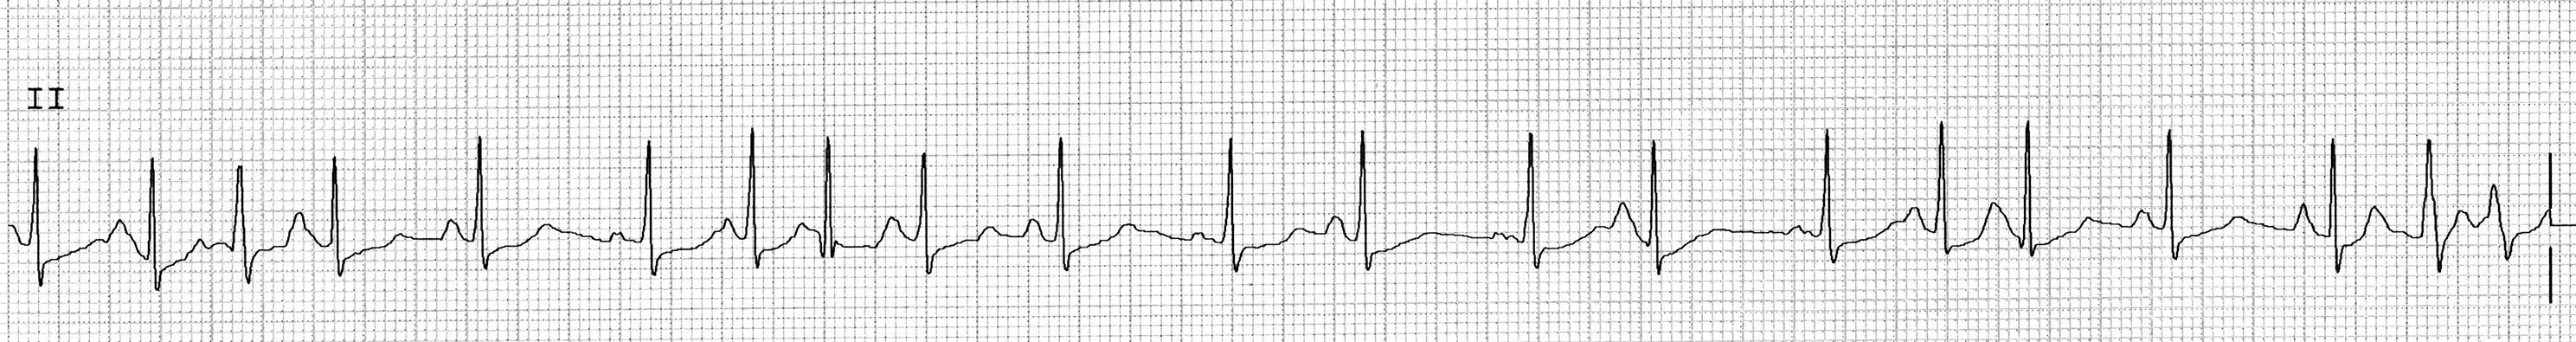

Figure 2. Sinus Tachycardia |

![]() |

Image courtesy of J. Stephan Stapczynski, MD |

Sinus tachycardia is defined by the presence of a regular rate and rhythm with a ventricular rate higher than 100 beats per minute with the following ECG features: the presence of upright P waves in leads I, II, and avL; a negative P wave in avR; and each P wave is followed by a QRS complex and T wave.33 (See Figure 2.) The QRS complex typically is normal and narrow (QRS duration < 120 msec) unless there is a preexisting conduction abnormality, such as a bundle branch block.